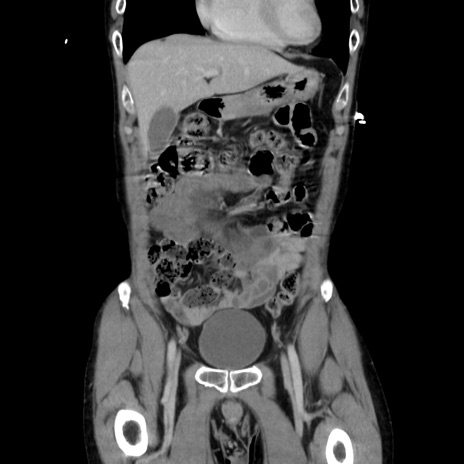

症例37(冠状断像)

【症例】40歳代 男性

【主訴】腹痛

【現病歴】4時間ほど前に電車に乗車中に臍部上より腹痛出現。徐々に増悪し起立困難となり、救急外来受診。生ものは数日食べていない。今朝お雑煮を食べた。

【身体所見】BT 36.8℃、BP 117/84mmHg、HR 91/min、SpO2 97%、苦悶様、腹部:臍上部広範囲圧痛あり、反跳痛±

【データ】WBC 8100、CRP 0.03